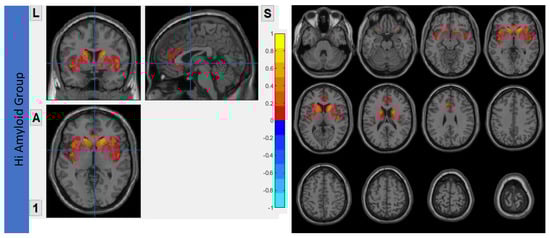

7.3. Within SN

Both HiAmy and LowAmy groups showed a positive correlation in the correlation map, ranges from r = 0.111 to 0.480, p < 0.05 and 0.165 to 0.451, p < 0.05 respectively, indicating the Aβ accumulation relates to the reduction of functional connectivity of that region. Details were shown in Figure 5.

Figure 5.

Correlation between Aβ burden and IFC in SN.